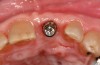

Fig 9. Palatal view (laboratory) of implant-retained crown with access opening ideally positioned in cingulum due to use of the angulated screw channel system.

Figure 9